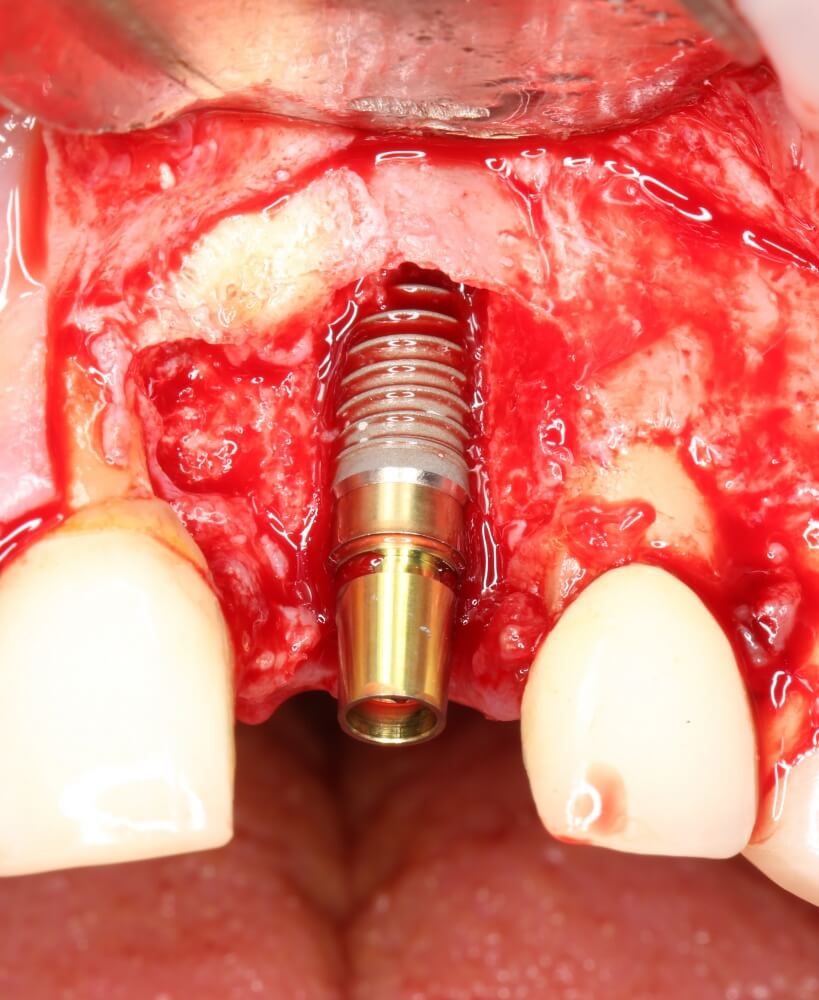

Рекомендации по установке имплантов. Для всех. Часть V.